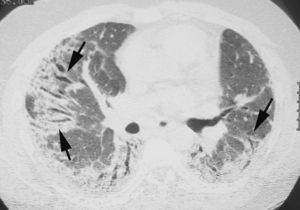

Patrón en «vidrio deslustrado»En la TCAR, el patrón en «vidrio deslustrado» se define como un tenue aumento de la densidad pulmonar de distribución a menudo geográfica, que no borra las estructuras vasculares adyacentes (fig. 4). Es un patrón inespecífico que se asocia a enfermedades alveolares, intersticiales o mixtas. En la enfermedad intersticial es visible cuando existe engrosamiento de los septos interlobulares o un grado mínimo de fibrosis. En la mayoría de los casos indica una patología potencialmente tratable. Se denomina patrón en «empedrado» (crazy-paving) a la superposición de un patrón lineal sobre un patrón en «vidrio deslustrado». Originalmente este patrón se describió asociado a la proteinosis alveolar, pero también se ha observado en la neumonía lipoidea exógena, en la hemorragia alveolar, en el daño alveolar difuso y en la infección por Pneumocystis jiroveci.

Imagen TCAR localizada en lóbulos inferiores que muestra un tenue aumento de densidad difuso, correspondiente a patrón en «vidrio deslustrado». Nótese que algunos lobulillos pulmonares no están afectados (flechas). Existe engrosamiento de las paredes bronquiales (cabeza de flecha) y una discreta dilatación esofágica (flecha negra).